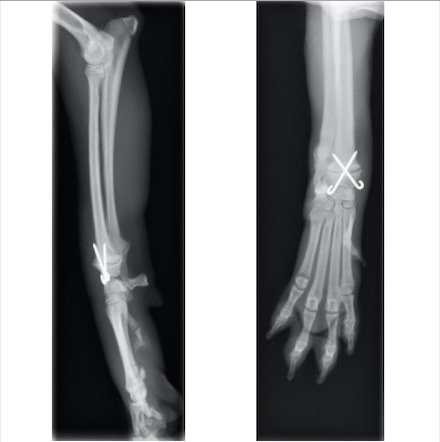

キルシュナーワイヤーを用いたクロスピン法にて整復しました

術後約1ヵ月後 挙上が認められなくなり、負重をかけての歩行が可能になったため抜ピンを行いました